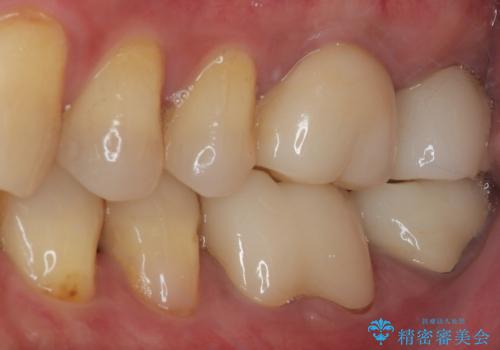

根管治療後は痛みもなくなりました。

強い咬合力による歯根破折を予防するためにナイトガードの使用も有効です。